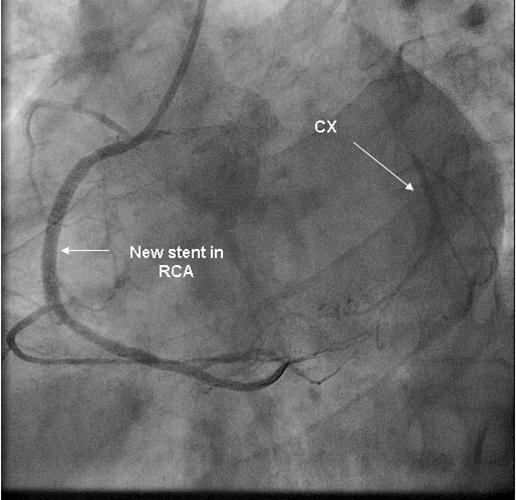

Coronary angiography was again performed. On injections into the left system, collaterals to the distal RCA were demonstrated (figure 1), arising from the left circumflex coronary artery (CX). Injections into the RCA demonstrated tight in-stent restenosis, (figure 2) and a drug eluting stent was successfully implanted. After the angioplasty, injections into the RCA were seen to retrogradely fill the CX (figure 3). The suspicion arose that maybe the left coronary artery had been inadvertently damaged during angiography, so the left coronary was again cannulated and injections performed, demonstrating entirely normal left main and CX arteries. However, the collateral flow that had previously been demonstrated from the CX to the RCA was no longer apparent. On review of the previous angiogram, it was noted that the RCA retrogradely filled the CX despite the original significant stenosis (figure 4). In essence, it became apparent that the bidirectional filling of the RCA from the CX and vice versa was in fact a direct continuity between the vessels and not collaterals, as free flow was noted from the RCA to the CX even when both arteries were completely patent.

Figure 3.New stent in RCA with retrograde filling of CX

New stent in RCA with retrograde filling of CX